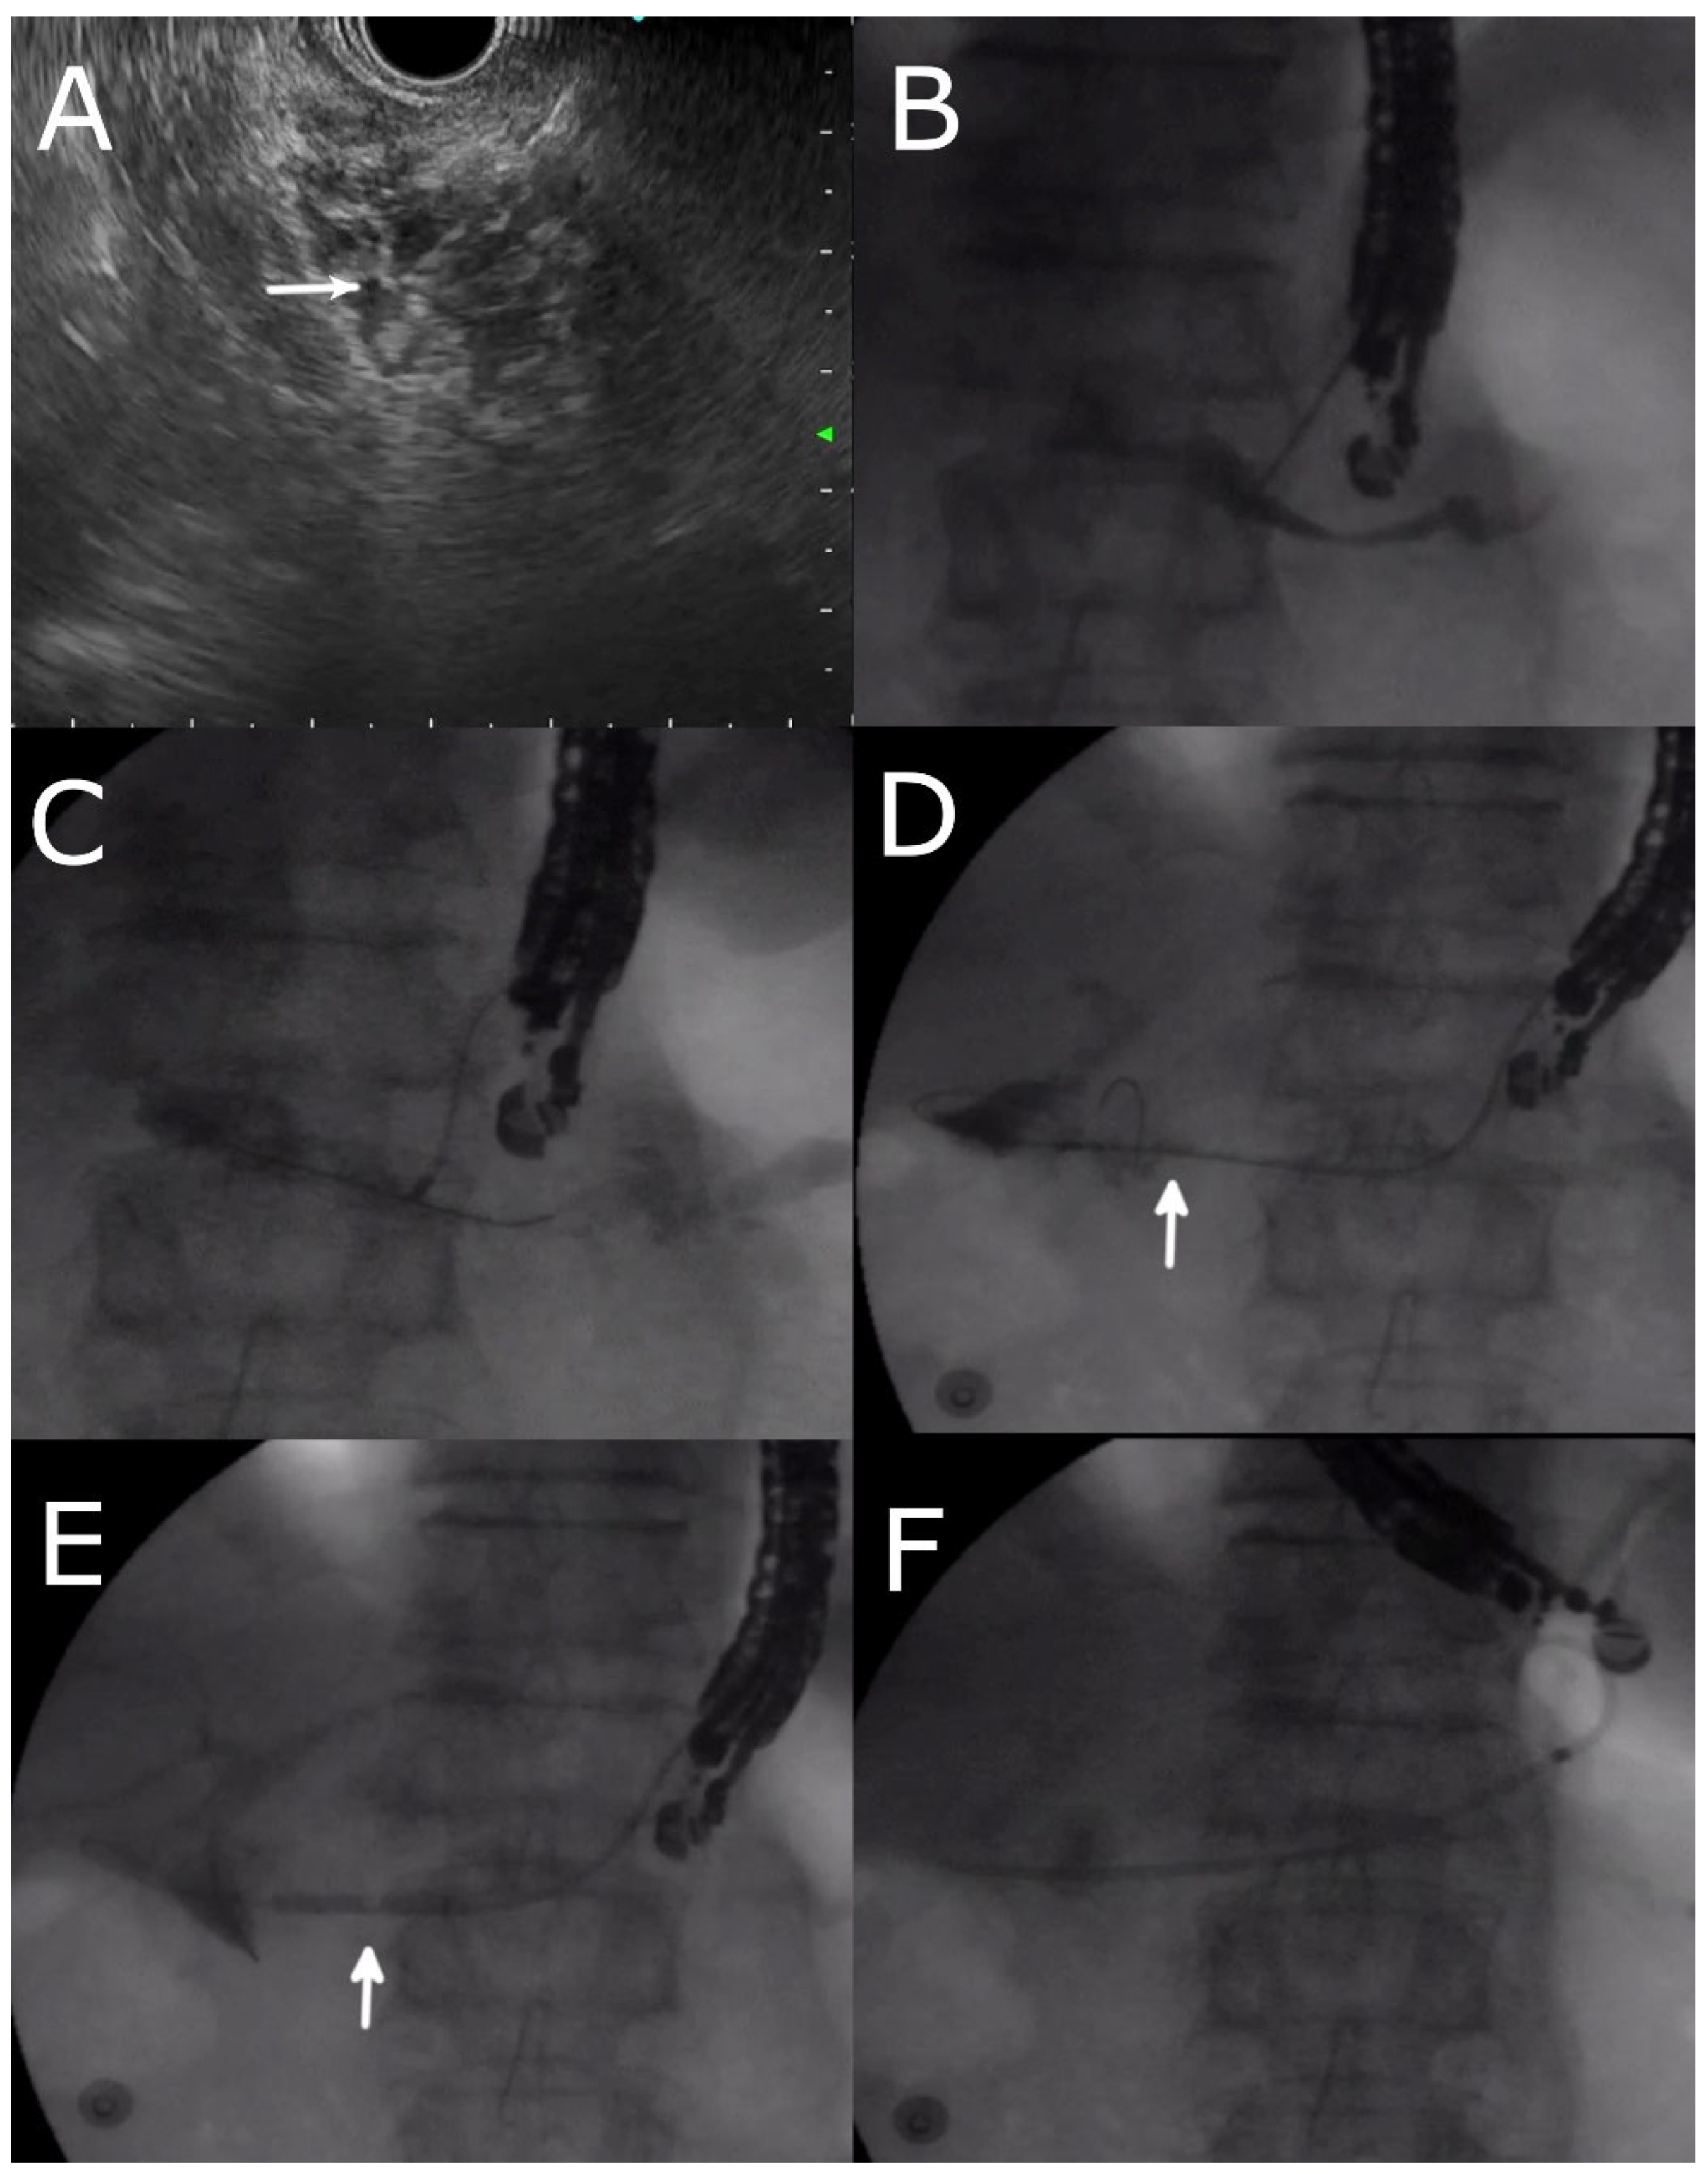

4.4. EUS- RV ERP

4.5. Transmural Approaches with Transpapillary or Trans-Anastomotic Stenting

4.6. Transmural Stenting with Antegrade/Retrograde Stenting